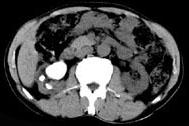

问题 男,53岁,反复右侧腰部隐痛不适2年余,CT如图所示,下列说法正确的是 ( )

选项 A、右肾自截 B、部分肾盏有扩张积液 C、右肾铸型结石 D、右肾钙化 E、右肾多发结石

答案 BCE